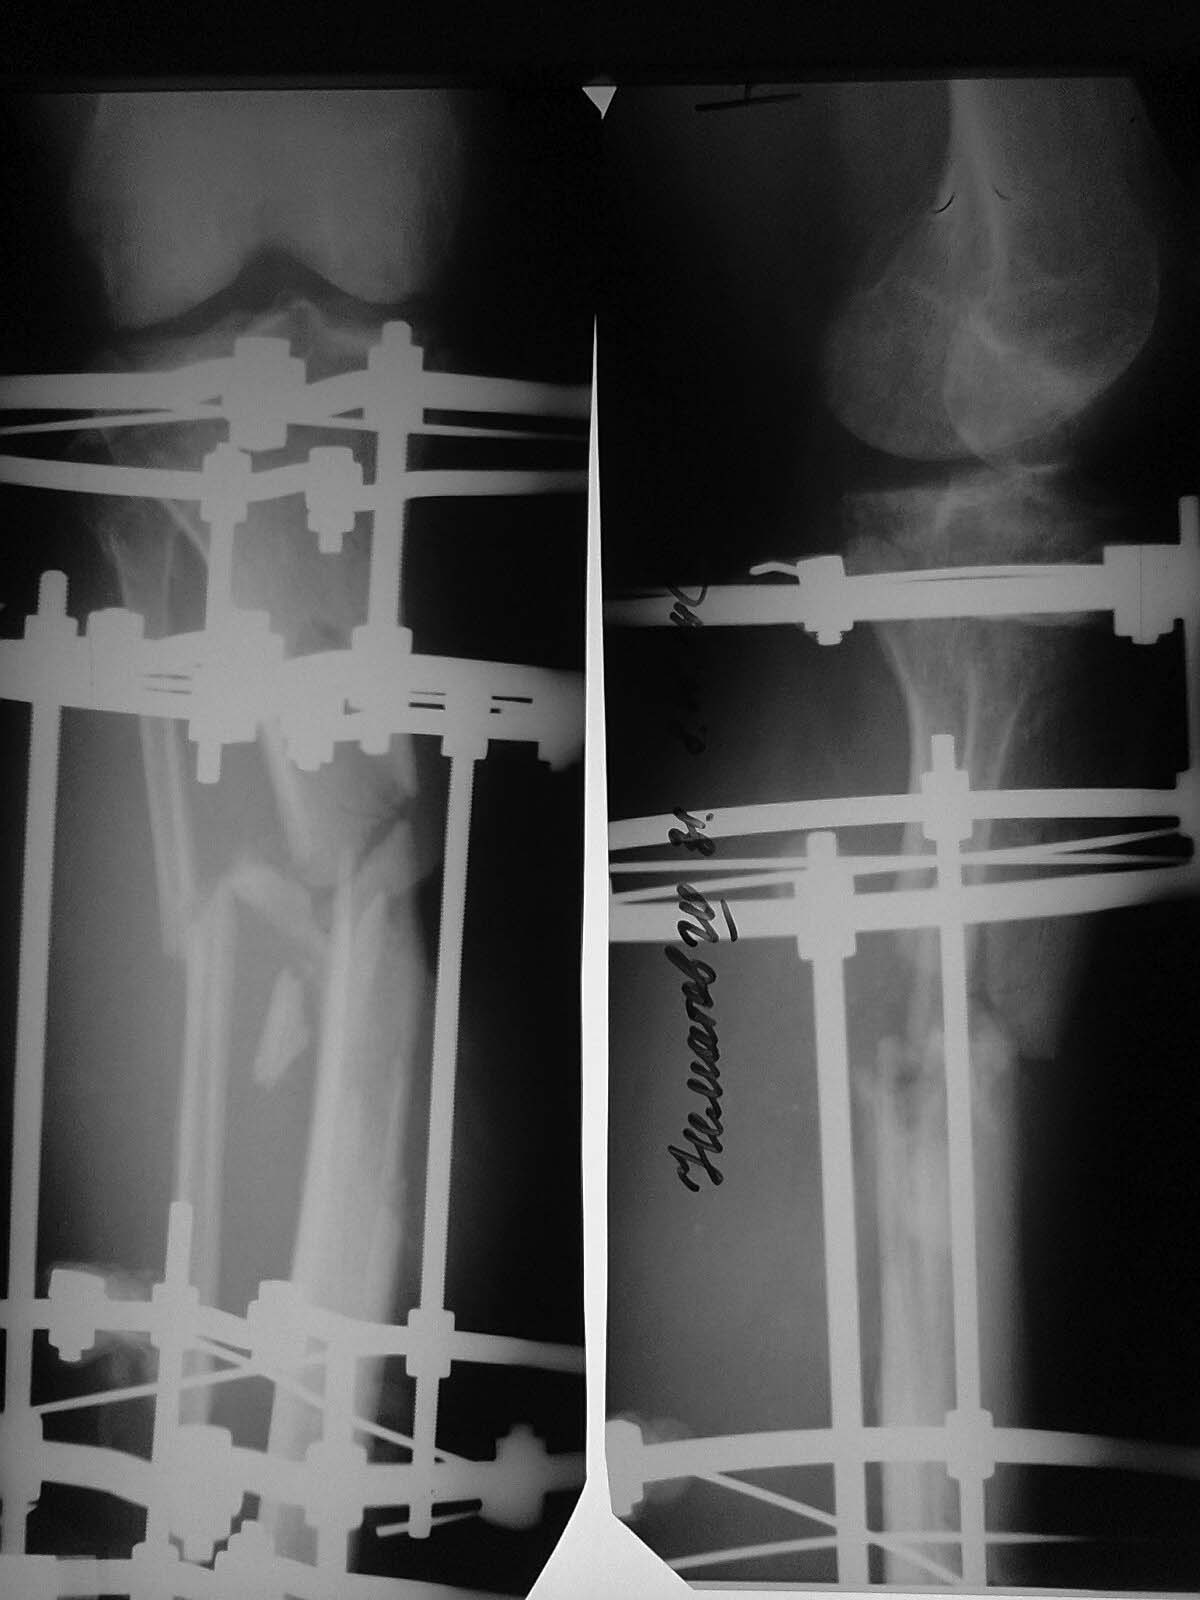

Доброго времени суток, уважаемые коллеги!Прошу Вашей помощи в лечении пациента Н. Пациент, 33 г. Травма в мае 2014 года в результате ДТП (сбит машиной). Оперирован в институте (или центре) травматологии и ортопедии одной из среднеазиатских республик (уроженец этой республики). Обратился к нам в августе, по поводу наличия гнойной раны внутренней поверхности голени с обильным отделяемым. (Рентгенограммы- фото 1). Выполнено: остенекрсеквестрэктомия, резекция концов отломков, перемонтаж аппарата (фото 2). Рана успешно зажила, пациент исчез из вида. Неделю назад пришел снимать аппарат с рентгенограммами (фото 3,4). Ходит с полной безболезненной нагрузкой на конечность, АВФ стабилен, раны от опорных элементов спокойны, отек конечности умеренный, в проекции бывшей гнойной раны- втянутый рубец (если необходим внешний вид конечности, то смогу выложить на следующей неделе,наверное). Учитывая большой дефект кости по задней поверхности кости, боимся, что при нагрузке без аппарата произойдет перелом. Вопрос: что делать? Наши варианты: 1.снять АВФ, рассверлить канал, установить штифт с антибактериальной мантией в виде "протеза" кости; 2.Резекция дефектного участка, остеотомия в н/3, перемонтаж АВФ и билокальное замещение дефекта. Что Вы посоветуете? Спасибо всем откликнувшимся.